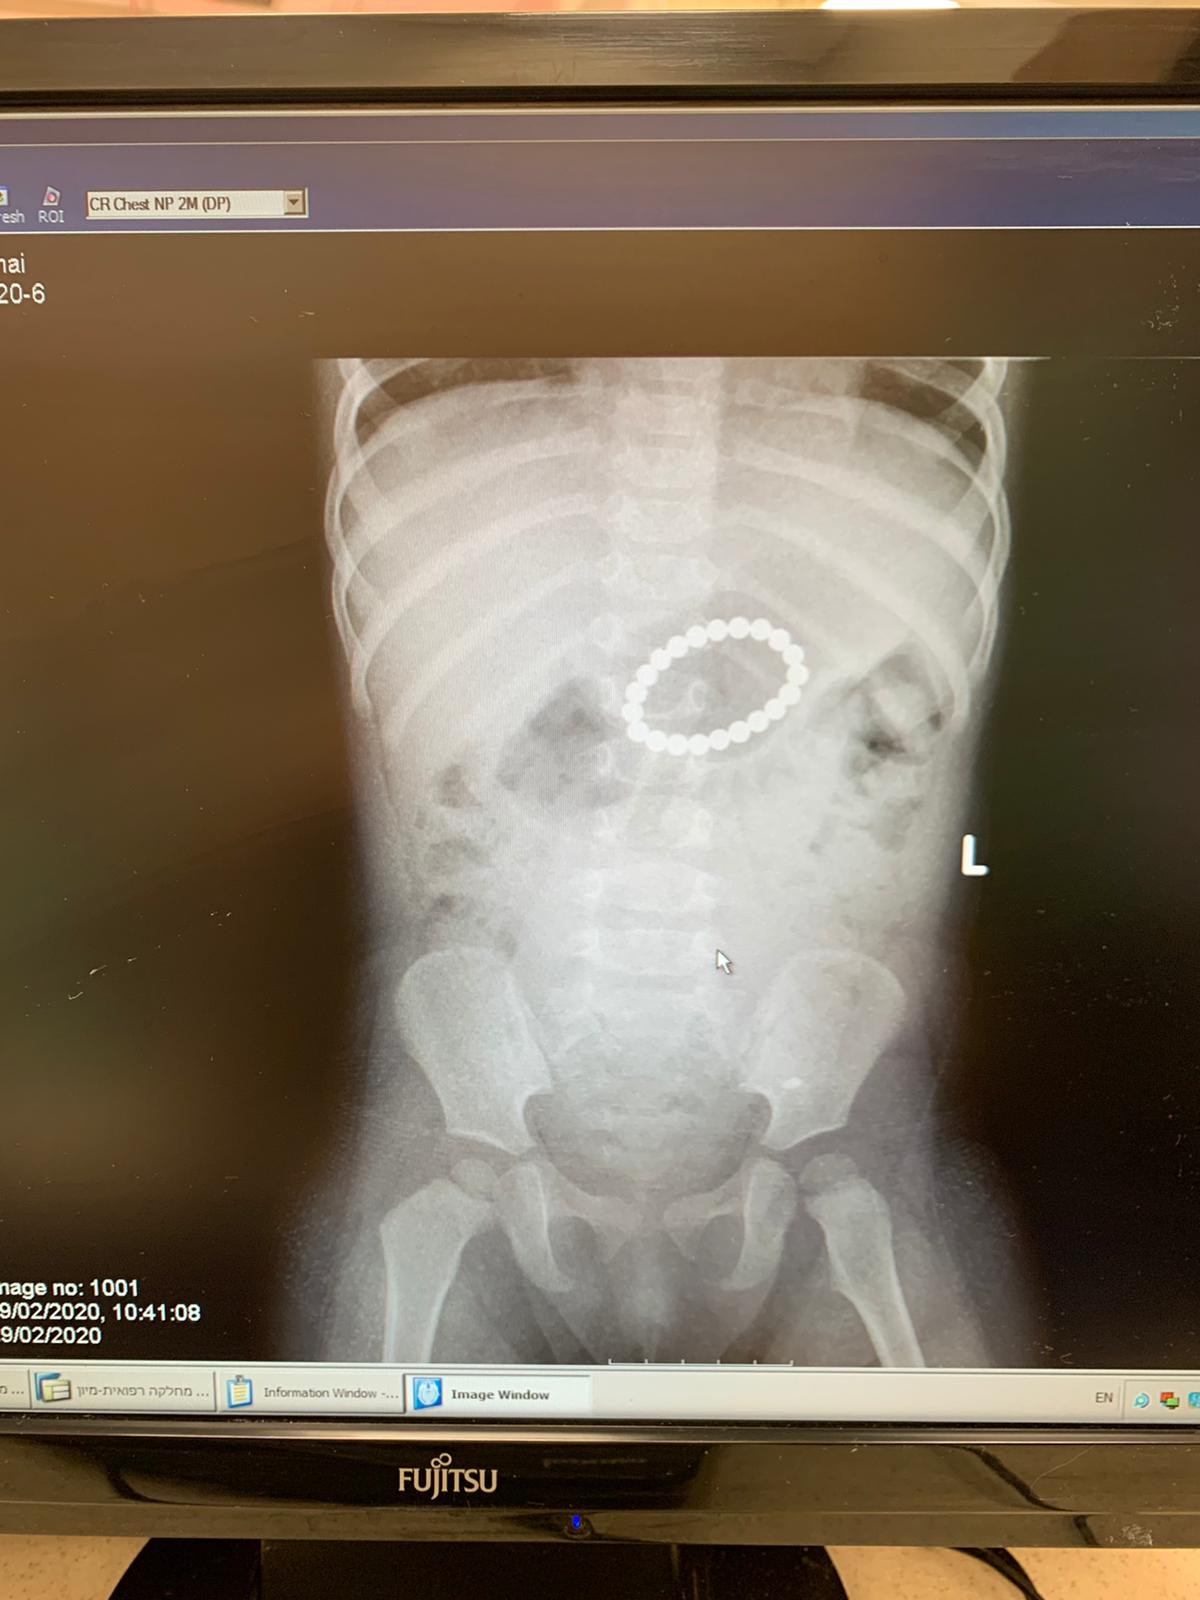

למלר"ד ילדים, במרכז הרפואי שמיר - אסף הרופא, הגיע אמש (מוצאי שבת) ילדה בת שנה וחצי, מאחד מישובי השפלה, לאחר שבלעה מספר רב של מגנטים שיצרו שרשרת מסוכנת שיכלה לגרום לפגיעה קשה במעי.

הילדה טופלה על ידי ד"ר נמרוד אופיר והועברה כעבור זמן קצר לחדר ניתוח - שם עברה גסטרוסקופיה דחופה על ידי פרופ' אפרת ברוידא מנהלת מכון גסטרואנטרולוגיה וממחלות כבד ילדים בבית החולים והמגנטים המסוכנים הוצאו מגוף הפעוטה בשלום.